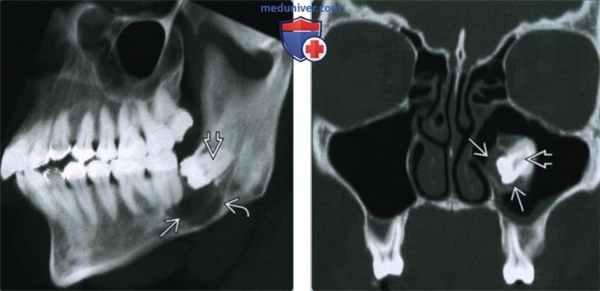

(Слева) На рисунке нижней челюсти (вид сбоку, кортикальный слой удален) показана «классическая» однокамерная фолликулярная киста, тесно прилежащая к коронке непрорезавшегося третьего моляра нижней челюсти, смещающего нижний альвеолярный канал.

(Справа) При корональной КТ в костном окне визуализируется импактный третий моляр нижней челюсти, возле которого находится киста с четко очерченной стенкой, обусловливающая расширение кости и истончение язычной кортикальной плааинки. Киста вплотную прилежит к коронке, не содержит обызвеавлений и не вызывает периоаальной реакции.

(Слева) КТ (суммационный рендеринг) позволяет продемонстрировать, как выглядит «классическая» фолликулярная киста однокамерная, хорошо отграниченная от окружающих тканей, расположенная в непосредственной близости к коронке импактного моляра нижней челюсти. Киста и моляр смещают нижний альвеолярный канал каудально.

(Справа) При корональной КТ в костном окне визуализируется импактный третий моляр верхней челюсти, смещенный в верхнечелюстную пазуху. Визуализируется также небольшая киста вокруг его коронки. Фолликулярные кисты чаще всего приводят к смещению зуба в направлении, противоположном вектору воздействия кисты.